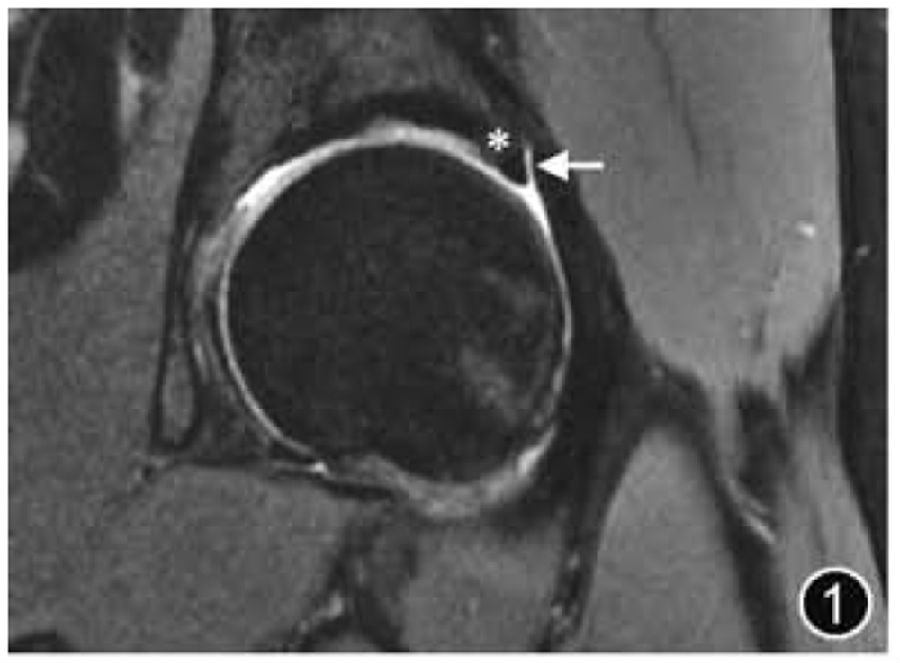

髋关节是由股骨头和髋臼组成的球窝关节,除中央凹外,股骨头周围有透明软骨覆盖,延伸至股骨头颈交界处。髋臼侧关节面呈新月形,关节软骨覆盖其前、上和后部区域,骨盆及股骨近端是红骨髓的储备部位,因此骨盆及股骨近端的骨髓信号通常不均匀(图1)。

图1 正常髋臼盂唇MRI图像。冠状面T2WI可清晰显示关节囊(↑)及盂唇软骨移行部(*)